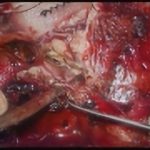

術中写真

摘出 中

摘出 後